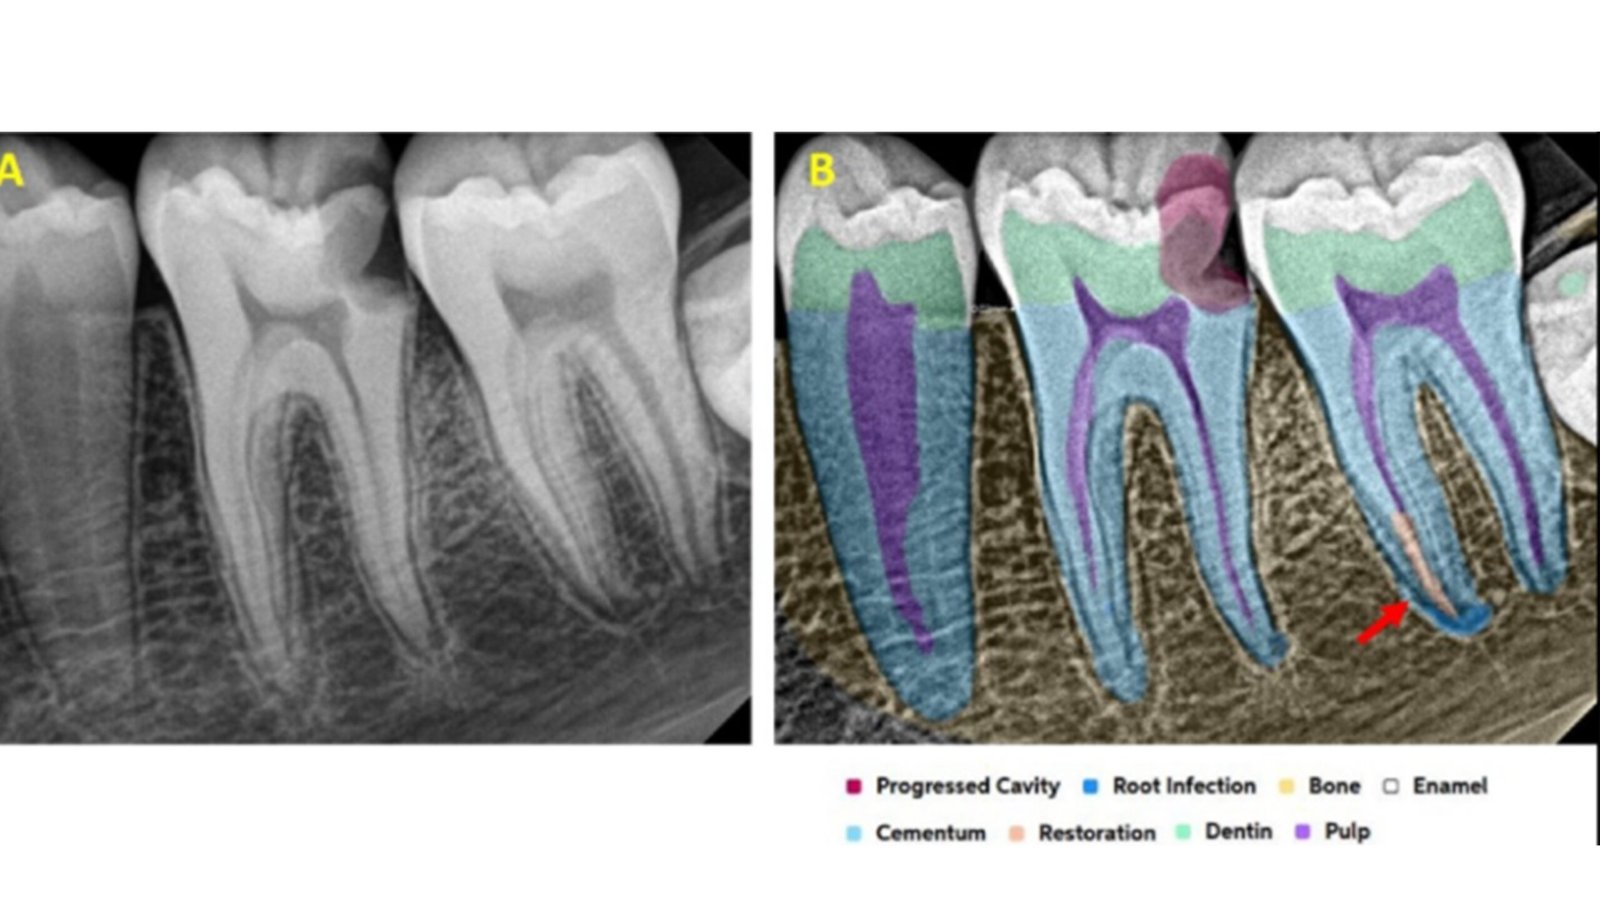

Leveraging AI-driven simulations, this segment integrates predictive modeling with clinical design. We optimize prosthetic, implant, and restorative solutions by forecasting mechanical performance, identifying risk areas, and supporting data-driven treatment planning.